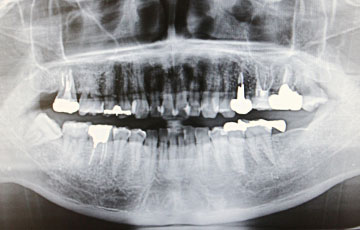

充実した設備体制

精密な診断を行うためのCTは欠かせない設備機器です。当院は、オールオン4に必要不可欠な設備と治療技術を整えており、多様な症例に対応できる環境をご用意しています。

海外の報告では、治療後10年以上が経過しても骨の吸収量は平均1.7mm未満にとどまったとされており、総入れ歯などと比較しても骨の安定が期待できる方法といえます。しっかり噛める環境を長く保ちやすい点が大きな特長です。

骨量や骨質に不安がある方には、6本で支える「オールオン6」という選択肢もあります。

顎の骨がやわらかい方や骨量が限られている方では、6本で分散して支えることで負担を軽減できる場合があります。骨の状態を精密に診断したうえで、より適した方法をご提案します。